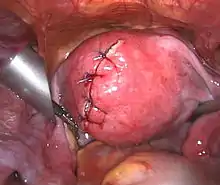

| Uterine fibroids as seen during laparoscopic surgery | |